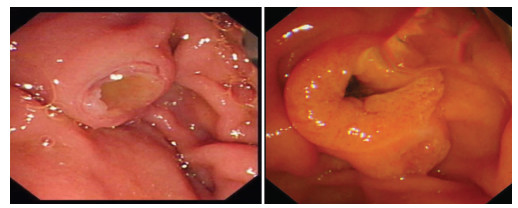

Endoscopic retrograde cholangiopancreatography combined with Spyglass in diagnosis of common bile duct papillary myxoma: A case report

Xuan DING, Linheng WANG, Gui JIANG, Yifei YUN, Xinyu LU, Yupu YAO

2021, 37(12): 2902-2904. DOI: 10.3969/j.issn.1001-5256.2021.12.034

Abstract(1315) HTML (221) PDF (2331KB)(47)

Abstract: